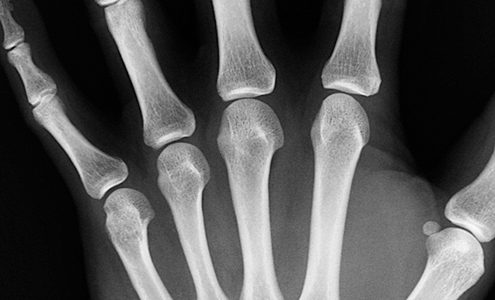

Bone Fractures: 10 Things Doctors Want You to Know

About 6 million people break bones in the United States every year. Here’s what three orthopedists want you to know about bone fractures.